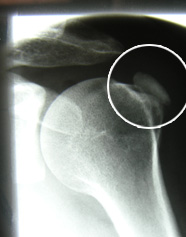

Abb 3; Das Röntgen zeigt den Kalk in der Schulter

Diese kann am Einfachsten und Sichersten mithilfe eines normalen Röntgenbildes gestellt werden (Abb 3). Auch eine Ultraschall-Untersuchung eignet sich dafür sehr gut.